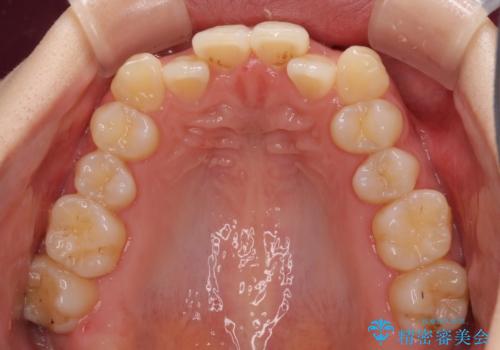

前歯のクロスバイトをインビザライン矯正で改善

- 前歯のデコボコと上下のクロスバイトを気にして来院された患者様です。

インビザラインを用い、IPR(歯と歯の間を削る)と歯列全体を拡大させることで、歯並びを整えていくこととしました。

上の前歯が下の前歯を乗り越える際、奥歯がほとんど咬めない時期があり、乗り越えた後も、インビザライン特有の奥歯の咬みにくさが続きました。

咬み合わせ改善のために治療期間を要しましたが、最終的に奥歯はしっかりと咬めるようになりました。